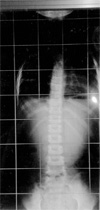

初診10歳

(a)H19/3

現在治療中

(b)H21/12

大塚整体指導装具の着用!

この装具は全国で一社のみ

39度   20度